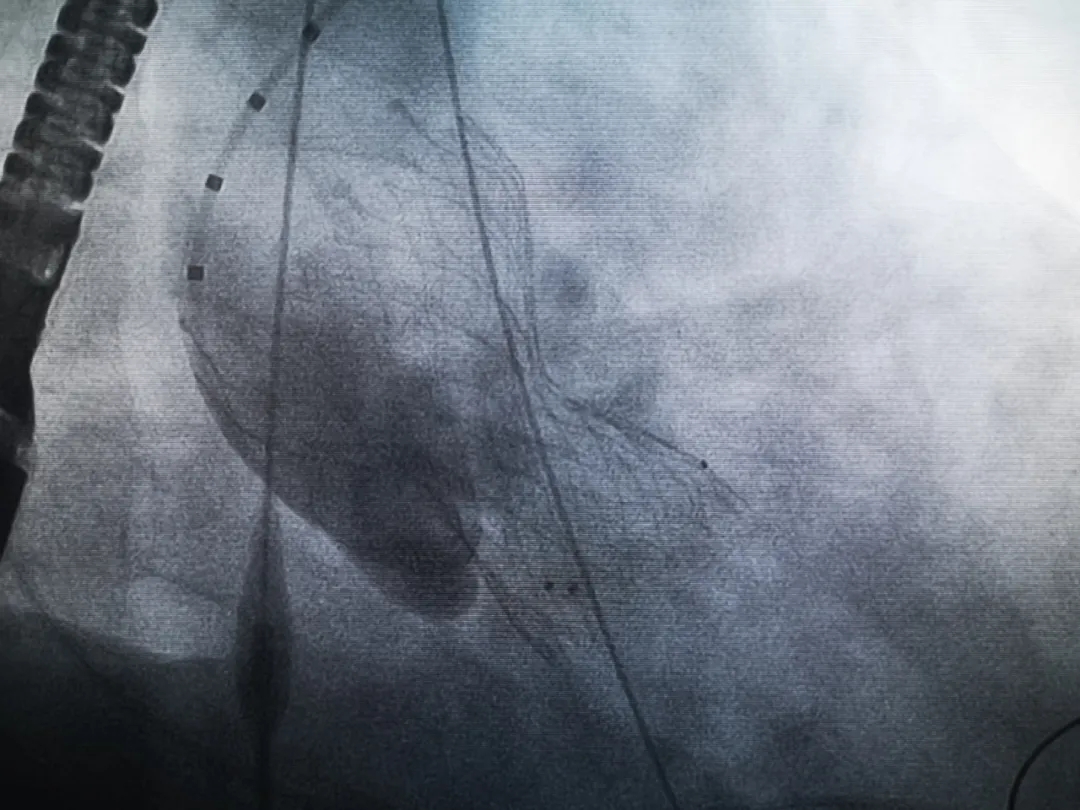

王子的手術(shù)被安排在周五。術(shù)前一天,TAVR團隊再次碰頭討論,從麻醉中血壓控制、球囊擴張、瓣膜釋放,到各種可能突發(fā)狀況的應(yīng)對,都提前制定了方案。尤其是瓣膜鈣化極為嚴(yán)重,對于擴張球囊型號的選擇、擴張的力度以及瓣膜植入后瓣周漏的發(fā)生預(yù)測,都具有很大挑戰(zhàn)。然而,如果沒有這些挑戰(zhàn),他又何必選擇我們呢!

手術(shù)過程緊張而有序,心臟沒有停跳,也沒有太大的血壓波動;球囊擴張的恰到好處,瓣膜釋放之后超聲醫(yī)生的評估是至關(guān)重要的,因為我們提前就準(zhǔn)備了后擴張,也準(zhǔn)備了瓣中瓣,甚至還準(zhǔn)備了瓣周漏封堵。所幸的是,超聲診療中心劉夢梅醫(yī)生說:沒有返流、沒有瓣周漏,瓣膜形態(tài)良好,跨瓣壓差約17mmHg(相較于術(shù)前的87mmHg還是可以接受的)。瓣膜置入的成功并不是慶祝的時候,從戰(zhàn)場撤退仍然需要謹(jǐn)慎。由于王子特別胖,腹股溝區(qū)脂肪尤為肥厚,在股動脈插管拔除、確認(rèn)搏動正常之后,便逐層縫合。同時為了美觀、縫合之后不至于鼓個包出來,我們又仔細(xì)剪除了部分脂肪。術(shù)后次日,王子便可以下床活動了。